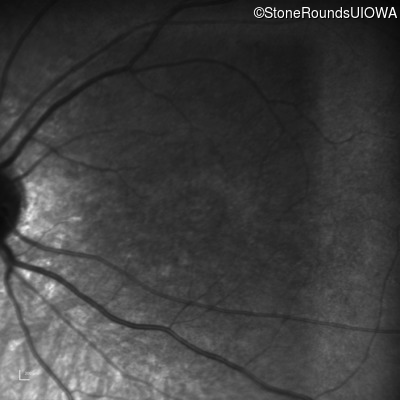

Infrared Fundus Photograph - Right - 5/200

Exemplar